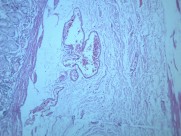

本病以胃粘膜萎缩变薄,粘膜腺体减少或消失,并伴有肠上皮化生,固有膜内多量淋巴细胞、浆细胞浸润为特点。本性胃炎的病因比较复杂,部分可能与吸烟酗酒和用药不量有关,部分由慢性浅表性胃炎迁移发展而来,还有部分属兔自身免疫疾病。